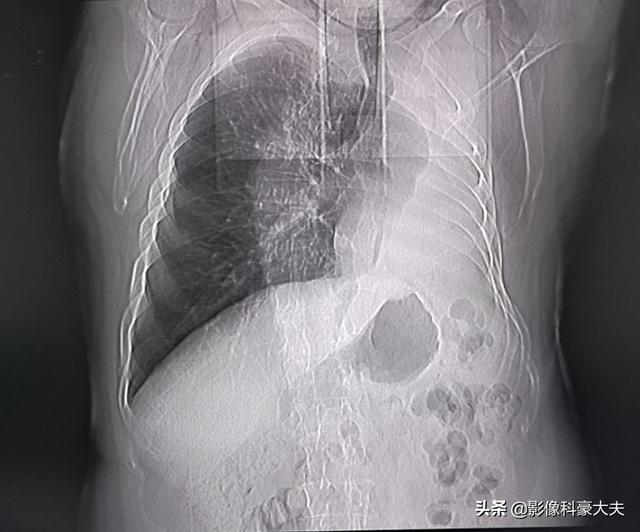

La récupération après une chirurgie du nodule pulmonaire est également liée au type de chirurgie pratiquée

La résection sous-lobaire (c'est-à-dire la résection segmentaire ou la résection en coin) a moins d'impact sur la fonction pulmonaire parce que moins de tissu pulmonaire est enlevé et qu'il reste plus de tissu pulmonaire normal. Si une lobectomie est pratiquée parce qu'une plus grande quantité de tissu pulmonaire est enlevée, il reste relativement moins de tissu pulmonaire normal, ce qui a un impact plus important sur la fonction pulmonaire et est plus susceptible de provoquer une gêne thoracique. Les photos suivantes montrent les poumons après deux résections différentes. La photo du haut montre la lobectomie du nodule pulmonaire inférieur droit, et vous pouvez voir que le poumon droit est significativement plus petit après l'opération. L'image du bas montre une résection sous-lobaire du nodule pulmonaire inférieur gauche, et vous pouvez voir que le poumon gauche conserve un volume plus important après l'opération.